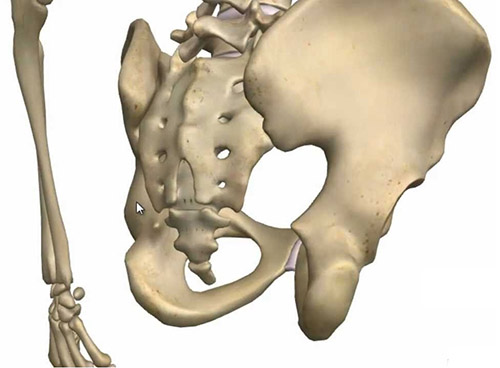

Neden leğen kemiği kayar?

Femur kemiğinin origosunun baş kısmı kendi yuvasından aşağıya ya da yukarı doğru kayıyor.Bu kayma sonucunda pelvis kemiğinin yanaklarından biri kayma sonucunda eğim kazanıyor.Eğim gerçekleştiğinde sacrumdan başlayıp lumbal bölgeyi ve sonrasında tüm vertebra disklerini kendi eksenlerinde döndürüyor.

Disklerin içi sıvı kıvamında ve dışa doğru koyulaşıp kabuklaşan bir yapıdadır,bu sayede kolay şekil değiştirebilir. Yukarıdan aşağıya bastırılan yüklerin bir tarafa eğik basması halinde bile bu yumuşaklık sayesinde bir alta yükü eşit dağıtır.Ani ve ters yüklenmeler sonucunda vertebra diskleri intervertebral disk kıkırdağının (pulpeus) etrafında sağ sola hareket edebiliyor.Bir disk döndüğünde nerelere zarar veriyor bunu bir disk kaydığında neler olur butonuna tıklayarak öğrenebilirsiniz